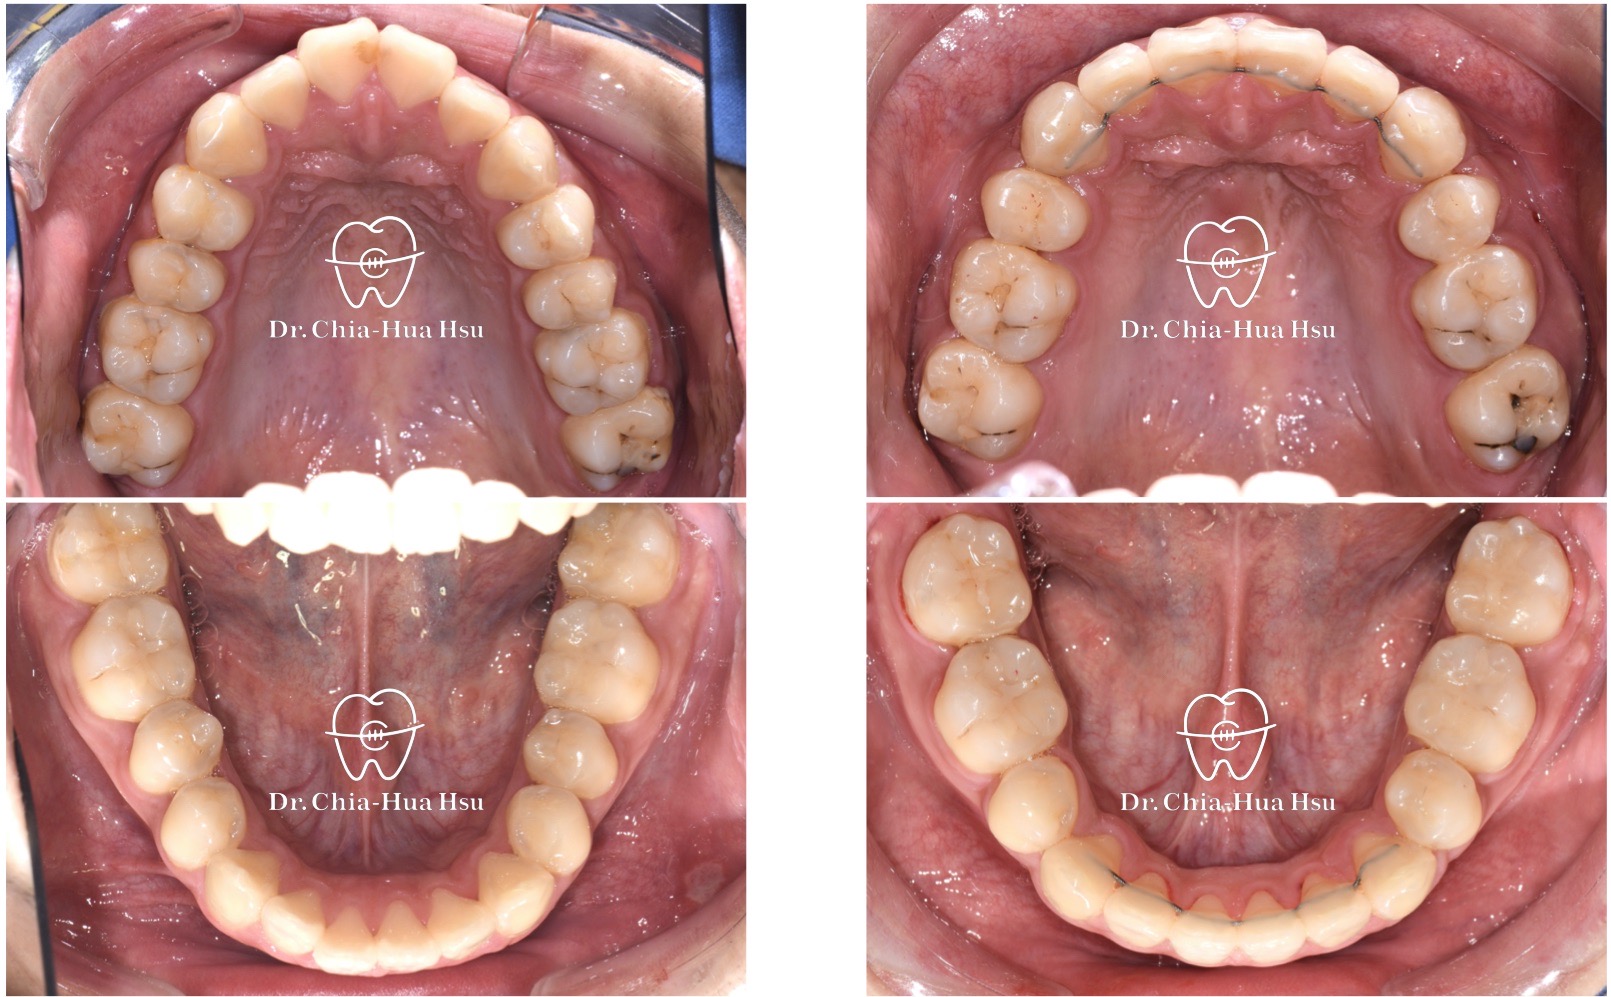

- 風趣幽默的20歲黃同學因為暴牙來院求診,由於患者下巴後縮又暴牙屬於複雜困難病例,還好病人十分配合療程,在許醫師悉心治療下,經歷兩年左右,讓治療順利完成。

- 病患主訴:暴牙、嘴凸、中線歪斜。

- 問題分析:患者是嚴重的骨骼二類咬合(Skeletal Class II)、下巴後縮、暴牙以及齒列不整齊。

- 治療方式:使用傳統金屬矯正器,並拔除四顆小臼齒,配合多支暫時性迷你骨釘來完成治療。

- 治療時間:2 年 2 個月。

治療前

治療後